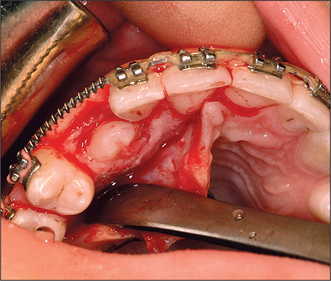

Attempts should be made to retain the keratinized tissues by employing displacement of the attached gingiva with apically or, occasionally, laterally repositioned flaps. The apically repositioned flap retains the mucogingival collar around the tooth and is displaced apically and sutured into place. The bunched gingiva will remodel as wound healing occurs (Fig. 12.1). If the tooth is misaligned, a bracket and gold chain may be etched to the canine to direct its eruptive path appropriately (Fig. 12.2).

image

Fig. 12.1 An erupted canine 3 months after exposure using an apically repositioned flap. The irregular gingival contour will gradually diminish with the passage of time.

Fig. 12.2 A bracket and gold chain bonded to the buccal surface of an exposed canine. The chain can be attached to a fixed appliance to direct the tooth into the correct location.